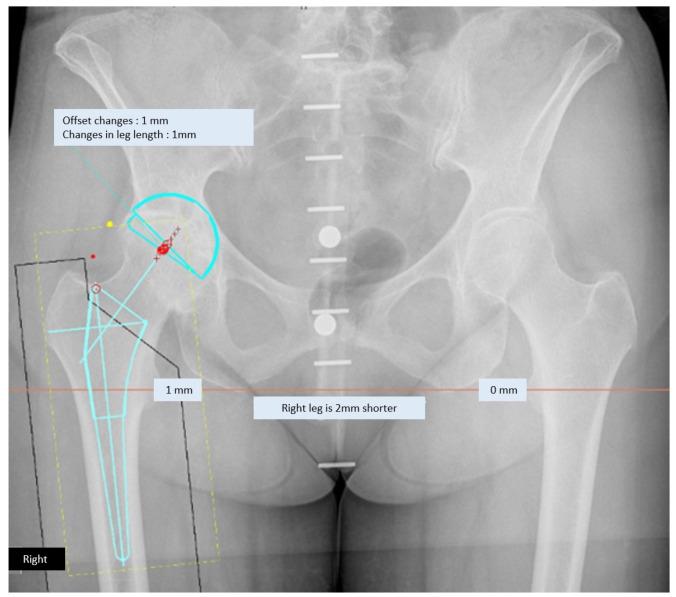

MATERIALS AND METHODS

A retrospective study was conducted. An analysis of 98 anteroposterior pelvic radiographs, which were individually templated by four surgeons (two hip surgeons and two orthopaedic residents) using TraumaCad digital planning, was performed. A comparison of preoperatively planned sizes with implanted sizes was performed to evaluate the accuracy of predicting component size. The results of preoperative planning performed by hip surgeons and orthopaedic residents were compared for testing of the planner's experience.

材料与方法

进行一项回顾性研究。对98张骨盆前后位X线片进行分析,这98张X线片由四位外科医生(两位髋关节外科医生和两位骨科住院医师)分别使用TraumaCad数字规划软件进行模板测量。将术前规划的尺寸与植入的尺寸进行比较,以评估预测假体组件尺寸的准确性。比较髋关节外科医生和骨科住院医师术前规划的结果,以检验规划者的经验。